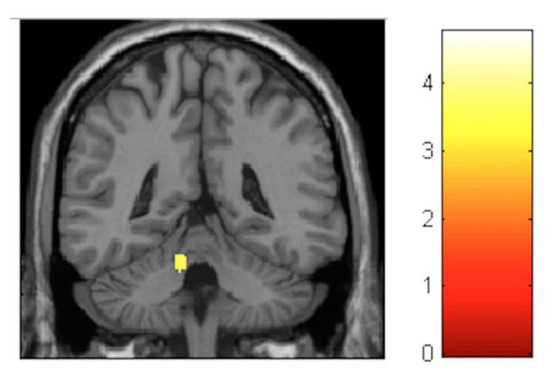

| Effect | Brain Region | Left Hemisphere MNI Coordinates (Cluster Size in Voxels) | T | d | Right Hemisphere MNI Coordinates (Cluster Size in Voxels) | T | d |

|---|---|---|---|---|---|---|---|

| Increment | Sensory-motor | −8, −32, 60 (314) | 5.17 | 0.39 | 11, −29, 60 (1087) | 6.09 | 0.41 |

| Decrement | Hippocampus | 27, −30, −6 (133) 23, −2, −17 (119) | 4.06 4.74 | 0.37 0.38 | |||

| Decrement | Insula | −33, −12, 18 (586) | 5.57 | 0.40 | 33, −17, 17 (797) | 6.17 | 0.41 |

| Decrement | Putamen | −26, 8, 6 (631) | 4.72 | 0.38 | 21, 11, 2 (134) | 4.22 | 0.38 |

| Decrement | Cerebellum | −11, −45, −23 (245) | 3.84 | 0.36 | 11, −65, −23 (224) | 3.99 | 0.37 |